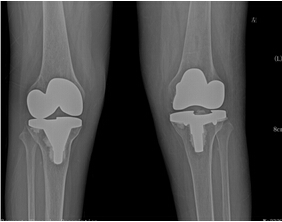

來院后,骨科二區(qū)唐雄主任、廖浩主治醫(yī)師熱情接待了她。經(jīng)查,患者為嚴重的類風濕性關(guān)節(jié)炎導致的雙膝關(guān)節(jié)破壞,雙膝關(guān)節(jié)內(nèi)翻畸形并嚴重的骨質(zhì)缺損,同時由于患者長期服用激素類藥物,其全身骨質(zhì)均有嚴重的骨質(zhì)疏松?;颊叩弥∏閲乐匦院螅械绞?、沮喪,唐雄主任信心滿滿地安慰道,“您這種情況行膝關(guān)節(jié)置換術(shù),就能徹底解決關(guān)節(jié)疼痛和雙膝關(guān)節(jié)不能活動的問題?!庇谑牵∪擞种匦氯计鹆藢ι畹南M?,并要求盡快進行手術(shù)治療。

考慮到患者為長期慢性病病人,唐雄主任決定先給患者疼痛程度更高的右側(cè)膝關(guān)節(jié)進行手術(shù)治療。經(jīng)過完善備血、調(diào)整激素用量等術(shù)前準備后,2015年10月10日,唐主任為患者進行了右側(cè)膝關(guān)節(jié)人工關(guān)節(jié)置換術(shù),術(shù)后患者恢復良好。右側(cè)膝關(guān)節(jié)疼痛解除,術(shù)后3天右下肢能下地活動。出院后,患者對右側(cè)膝關(guān)節(jié)置換術(shù)的效果非常滿意。 2016年7月17日,唐主任為該患者再次進行了左膝關(guān)節(jié)人工關(guān)節(jié)置換術(shù)?;颊咝g(shù)后3天就能下地活動。現(xiàn)在她的臉上又出現(xiàn)了燦爛的笑容,她逢人就說,要是早一點來手術(shù)治療,就能早一點擺脫病痛的折磨了。